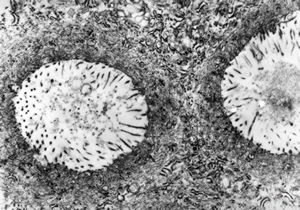

F,68y. | APUD carcinoma

F,68y. | APUD carcinoma

F,68y. | APUD carcinoma

F,68y. | APUD carcinoma

F,68y. | APUD carcinoma (Bodian siver impregnation)